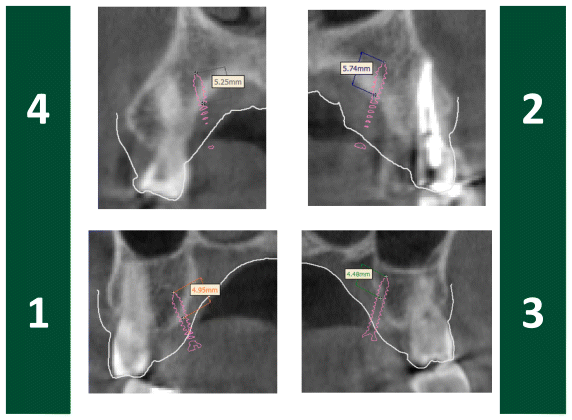

The surgical planning was predicated on high-resolution three-dimensional DICOM imaging, facilitating a comprehensive assessment of the maxillary bone structures and their spatial relationship with the dental roots. The STL file of the patient’s upper arch was acquired and digitally aligned with the CBCT scan, thus enabling accurate anatomical reconstruction and enhancing the virtual planning of screw placement (Figures 1 and 2).

As delineated by Haas Junior et al. (13), the STL file of the expander screw was incorporated and precisely positioned in the desired location. The placement of miniscrews was meticulously planned, maintaining an approximate distance of 1.0 mm from the contour of the palatal mucosa, utilizing the file addition and positioning tool (Figure 1). Particular attention was given to the correct orientation of the screws (Figure 2), ensuring respect for anatomical structures, thereby avoiding injury to the dental roots or periodontal tissue, and guaranteeing an appropriate insertion depth into the bone.

Subsequently, a three-dimensional reconstruction of the processed data was carried out to acquire a spatial overview of the relationships between the planned anchorage screws and the roots of the dental elements in the upper arch (Figure 3). The positioning methodology guaranteed the optimal allocation of expansion forces while minimizing potential risks to neighboring dental roots.

A cone beam computed tomography (CBCT) is necessary to determine the appropriate placement of the expander and miniscrews, as well as their dimensions. The acquired DICOM (Digital Imaging and Communications in Medicine) images are utilized for three-dimensional reconstructions. Subsequently, the three-dimensional tomographic image must be oriented to standardize the head position relative to the Frankfurt plane (or L-Po-o R), ensuring it is parallel to the axial plane. The Nasion-Anterior Nasal Spine plane should be perpendicular to the Frankfurt plane (13).